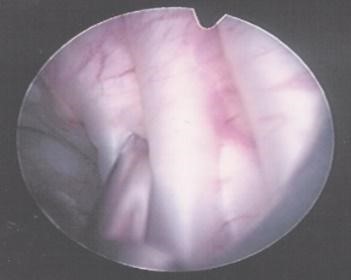

● 膀胱肉毒桿菌素注射

膀胱肉毒桿菌素注射、膀胱頸切開術、尿道括約肌切開術、膀胱擴大整型手術、尿道懸吊手術等。創新醫療有機械手臂自體膀胱擴大整型術,人工括約肌植入術。